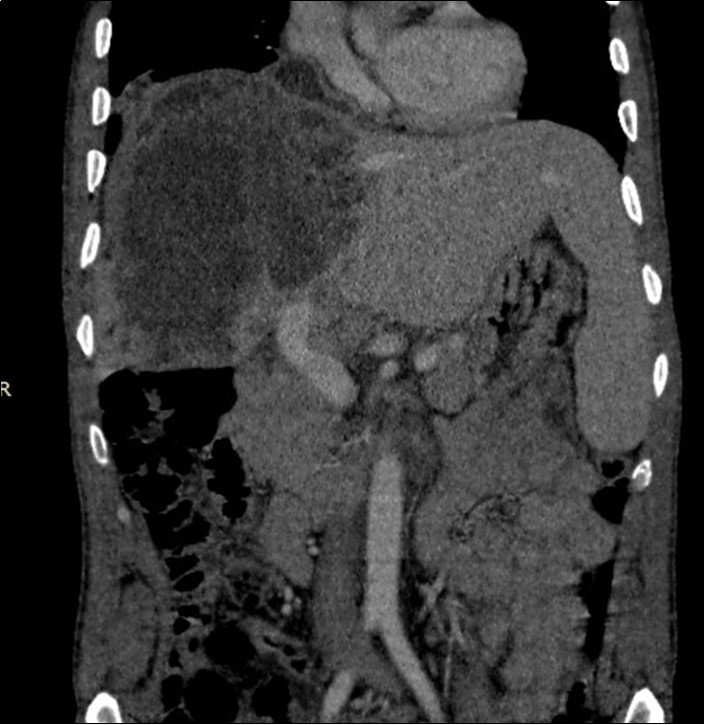

A 50-year-old man, was referred to our center for abdominal pain that had persisted for 1 month with marked loss of weight. An abdominal ultrasound completed by CT scan revealed a tumor of 15 centimeters of main axis of the right liver associated in contact with the portal vein associated with bilateral pulmonary nodules (Figure 1, Figure 2). Family and personal history for tuberculosis were negative. On admission, there was no fever, the abdomen was soft and non-tender, and there was a painful hepatomegaly without palpable mass. Blood showed anicteric cholestasis. Hydatid serology as well as tuberculin skin tests were negative. Upper and lower digestive endoscopy as well as tumor markers were normal. An ultrasound-guided fine-needle biopsy showednecro-inflammatory changes of the liver parenchyma without any signs of malignancy or specificity. Concerning the pulmonary lesions, there were no proof of active tuberculosis (sputum examination and bronchoalveolar lavage showed no BK). Patient received empiric antibiotherapy (amoxicillin and clavulanic acid) with regression of the pulmonary lesions in the control X Ray.

Figure 1.Coronal CT scan showing the hypodense heterogeneous liver mass in contact with the portal vein and diaphragm